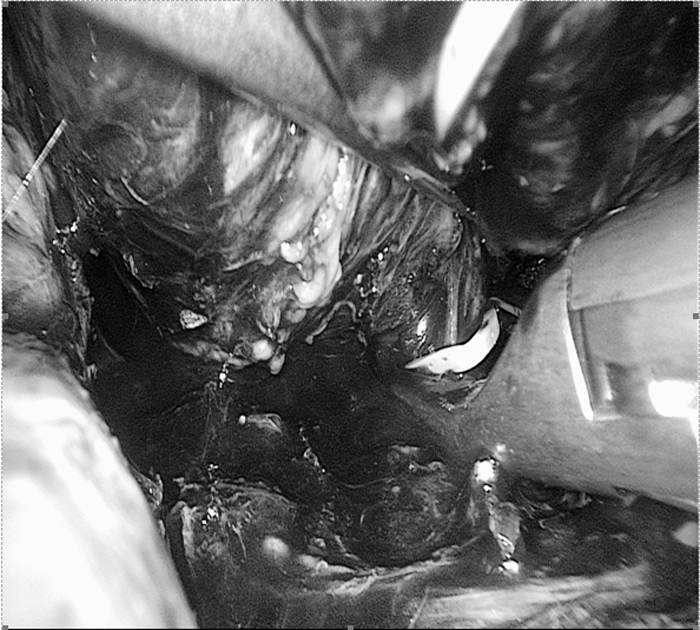

手術(shù)中影像(圖片已做處理)

??? 麻醉科余功敏主任醫(yī)師已經(jīng)和萬(wàn)醫(yī)生配合完成了好幾臺(tái)嗜鉻細(xì)胞瘤的手術(shù)。手術(shù)當(dāng)日,余功敏在完成了深靜脈穿刺、動(dòng)脈穿刺和氣管插管后,又在一旁準(zhǔn)備了自體血回輸設(shè)備,說(shuō):“你放心開(kāi)始手術(shù)吧!”術(shù)中雖然經(jīng)歷了血壓飆升和血壓下降,但余功敏鎮(zhèn)定自若,降壓藥和升壓藥輪流上陣。經(jīng)過(guò)嚴(yán)密的麻醉監(jiān)護(hù)、精確的術(shù)中操作,一個(gè)小時(shí)后在腹腔鏡下有驚無(wú)險(xiǎn)地順利切除腫瘤。手術(shù)順利,老太太術(shù)后恢復(fù)快,第五天就出院。